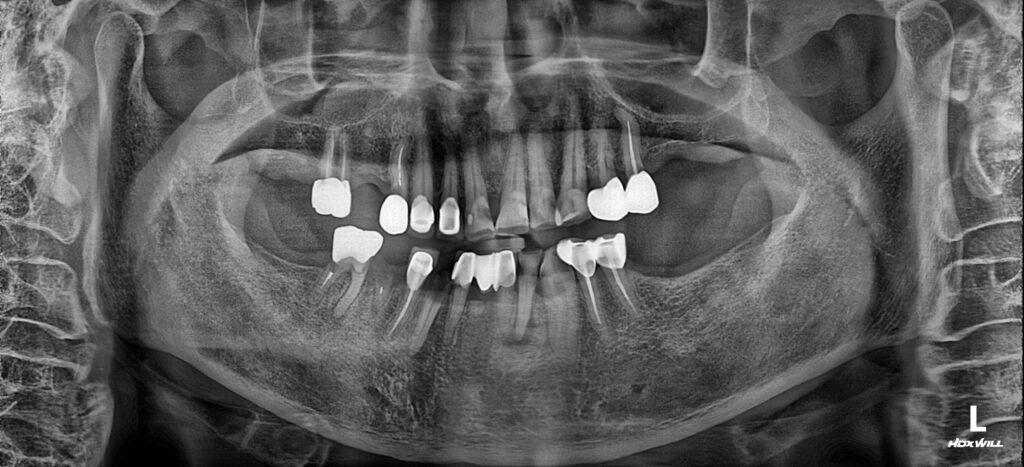

26.02.02

아래 임플란트와 신경치료, 보존치료가 마무리된 모습입니다. 환자분의 경우, 치료가 필요한 치아가 많았지만 아래를 먼저 마무리 한 상태에도 너무 편안하게 식사를 하시게 되었고, 통증이 사라져서 일상이 많이 편안해지셨다고 하셨어요!

단, 아직 상악 치아들 치료가 남아있으며 환자분께서 아직 구강관리가 어려우셔서 부러진 치아들도 발생하여 서울화이트S치과는 모든 치료가 온전히 마무리 될 때까지 책임지고 진행해 드릴 것을 약속드렸습니다.